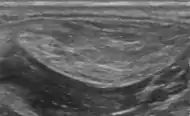

A lipoma is a non-cancerous soft tissue tumor made of fat tissue.[1] They are generally soft to the touch, movable, and painless.[1] They usually occur just under the skin, but occasionally may be deeper.[1] Most are less than 5 cm in size.[2] Common locations include upper back, shoulders, and abdomen.[4] A few people have a number of lipomas.[3]

• Superficial subcutaneous lipomas, the most common type of lipoma, lie just below the surface of the skin.[13] Most occur on the trunk, thigh, and forearm, although they may be found anywhere in the body where fat is located.